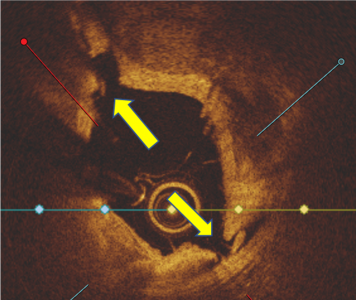

OCT Imaging Confirmed High Fracture Depth and Width Even in Complex Calcified Lesions

Calcium score 2, Nodule Present

2EXR_Clinical-Evidence_Calcium-Score-2_1.jpg

EXR_Clinical-Evidence_Calcium-Score-2_2-1.png

OCT analysis demonstrated effectiveness of the novel mechanism of action (N = 32; L = 32#)

• Calcium fracture and fragmentation was identified in >90% of the calcified lesions with multiple fractures in 75% lesions

• Calcium fracture depth of 0.81mm ± 0.33 and fracture width 0.66mm ± 0.29

• Deep calcium fractures in eccentric and concentric calcified lesions post HC-IVL, confirming the mechanism of action of HC-IVL.